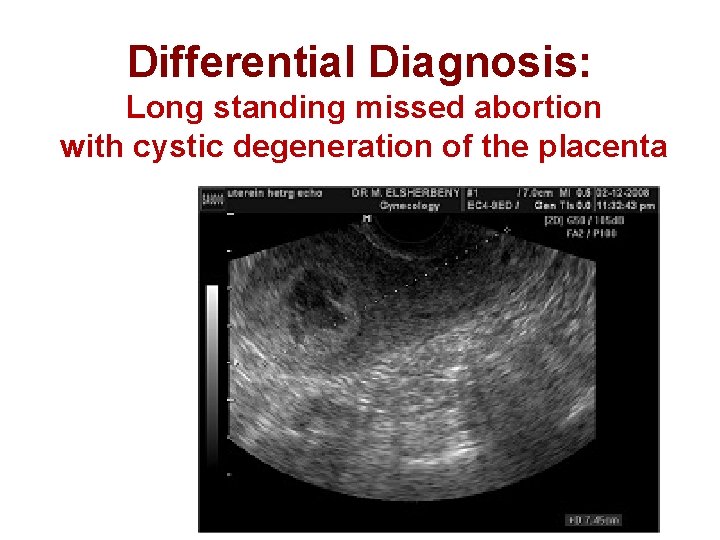

Differential Diagnosis: Long standing missed abortion with cystic degeneration of the placenta

What Is The Recommended Subsequent Test ? β subunit h. CG The B subunit h. CG assay: 195, 000 ml. U/m. L Then 1 -What is the most likely diagnosis? 2 -How can the patient be managed?

1 -What Is The Most Likely Diagnosis? The snowstorm pattern on U/S& The abnormally high h. CG level are diagnostic of Vesicular Mole Probably complete V. mole

Why It Is Probably Complete V. Mole? It demonstrates the typical U/S appearance of complete V. mole : a complex, echogenic intrauterine mass containing many small cystic spaces. Fetal tissues and amnionic sac are absent However the final differentiation is after histopathology.